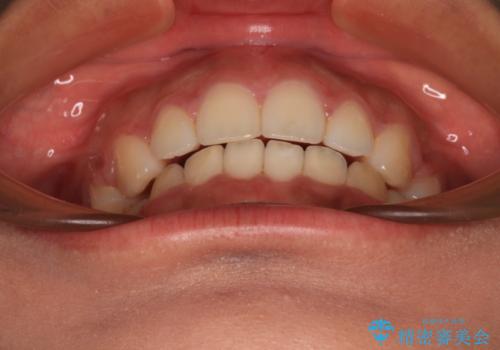

- 出っ歯と口の閉じにくさ、デコボコを気にして来院された患者様です。

口元の突出感を改善するため、上下左右第一小臼歯4本の抜歯を行い、ワイヤー装置による矯正治療を行うこととしました。

舌の突出癖により上下前歯は非接触であり、非常に前方に飛び出している状態でした。

舌のトレーニングをしっかりと行っていただき、口の閉じやすい歯並びに仕上げることができました。